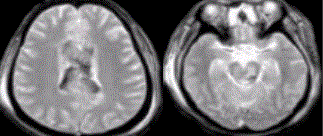

- [材料题] 患者,男性,27岁。车祸外伤后昏迷,X线平片与CT未见明确骨折及颅内血肿,MR表现如下图。

- 简答题1、请问该患者诊断应该是什么?

- 简答题2、请问该病影像学有哪些表现?